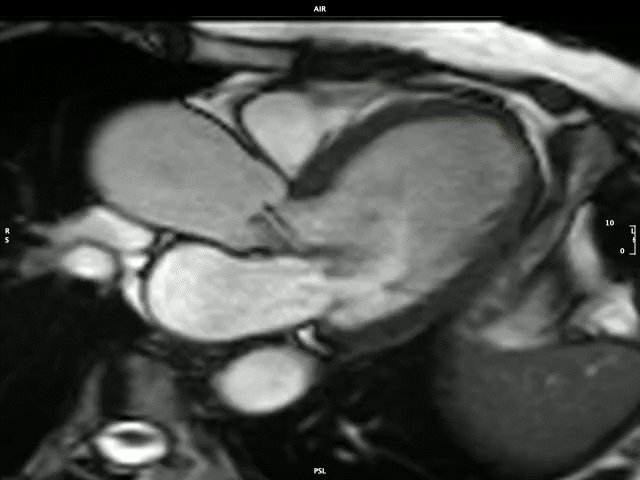

The Division is known locally and internationally as a centre of imaging excellence within both the clinical and research setting. The imaging expertise unit stretches across modalities, including 2D and 3D echocardiography, and state-of-the-art cardiovascular magnetic resonance (CMR) imaging that includes multiparametric mapping demonstrated below.

Severe aortic regurgitation

Image by: Dr P-P Robbertse